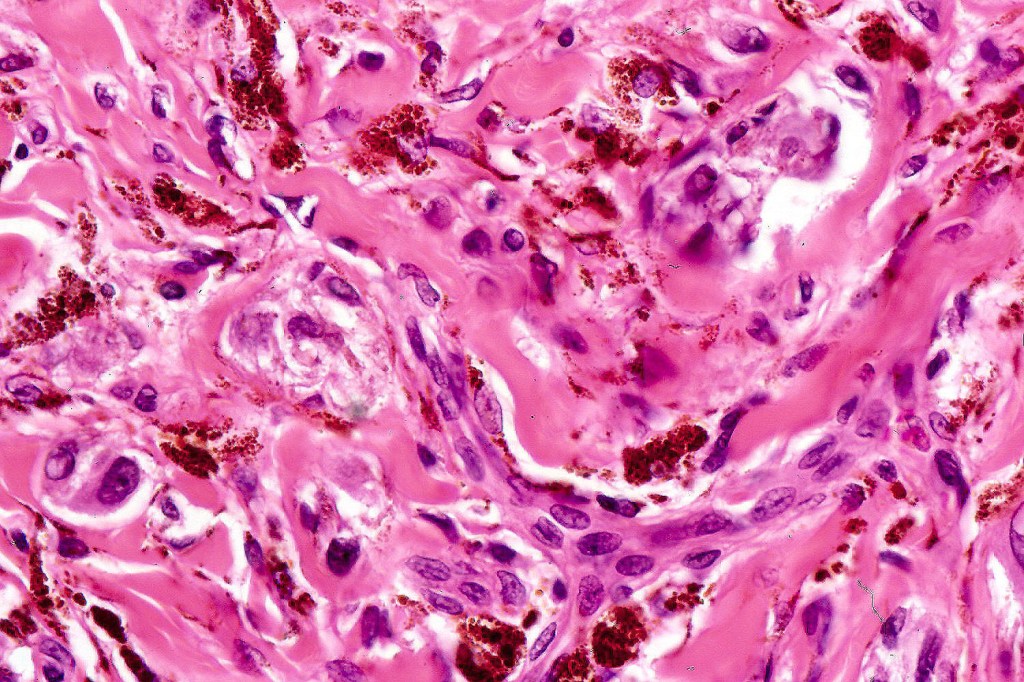

•Admixture of spindle cells, pigmented bipolar or dendritic cells & melanophages

•Cytoplasm is pale and nuclei are small with inconspicuous nucleoli

•An alveolar pattern is characteristic particularly with clear cell nodules

•Mitoses are typically very sparse or absent

•No atypical mitoses

•Multinucleate giant cells sometimes present